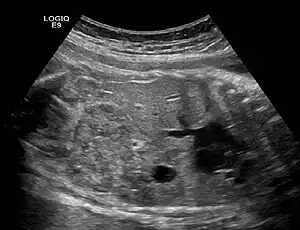

| Ectopic crossed fused kidney in a fetus approx. 34 weeks | |

Ectopic kidney describes a kidney that is not located in its usual position. It results from the kidney failing to ascend from its origin in the true pelvis or from a superiorly ascended kidney located in the thorax.[1]